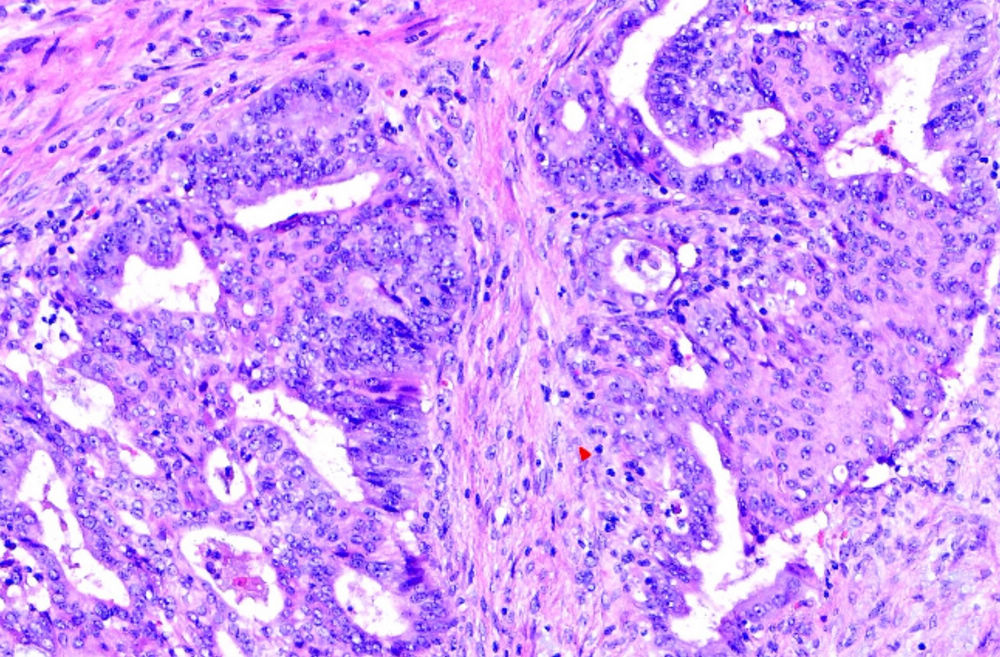

小土豆跟着农人老师学本领-食道手术切除 粘膜表面鳞状上皮缺乏异型性 基底部细胞排列紊乱 浸润性生长  鳞癌